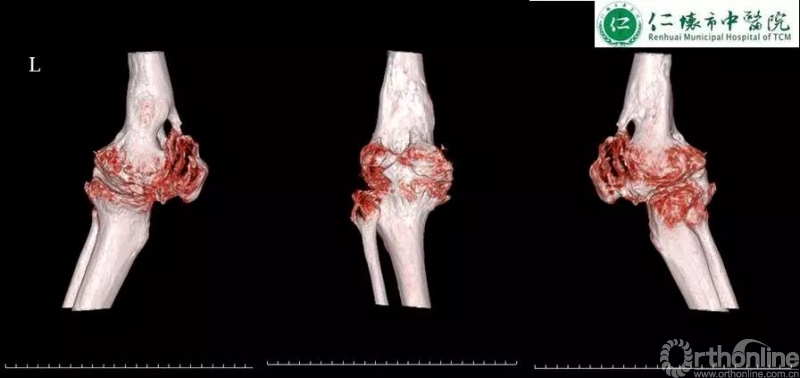

课程分享结束后,进入病例分享环节,四家与会医院分别展示各自病例并就术中存疑和李子剑教授探讨取经。仁怀市中医院分享了一例经典的使用ACCK假体复杂右膝关节置换手术:

术前影像:

术前规划:

李子剑教授对仁怀市中医院这例手术的术前规划方案和假体选择表示充分的肯定,对术后力线及假体位置同样表示赞赏。对于仁怀市中医院各位主任提出的关于未来左膝关节置换的相关问题,李教授给出了使用定制化导板截骨的中肯建议,并分别分析了ACCK,AHK和肿瘤假体在这例病例中应用的可能性及利弊,各位专家集思广益,不断碰撞出学术的火花。